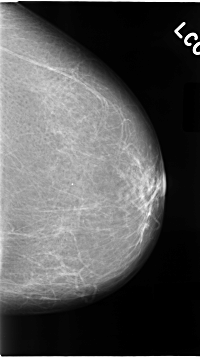

C_0073_1.LEFT_CC

LEFT_CC LINES 4656 PIXELS_PER_LINE 2592 BITS_PER_PIXEL 12 RESOLUTION 50 NON_OVERLAY